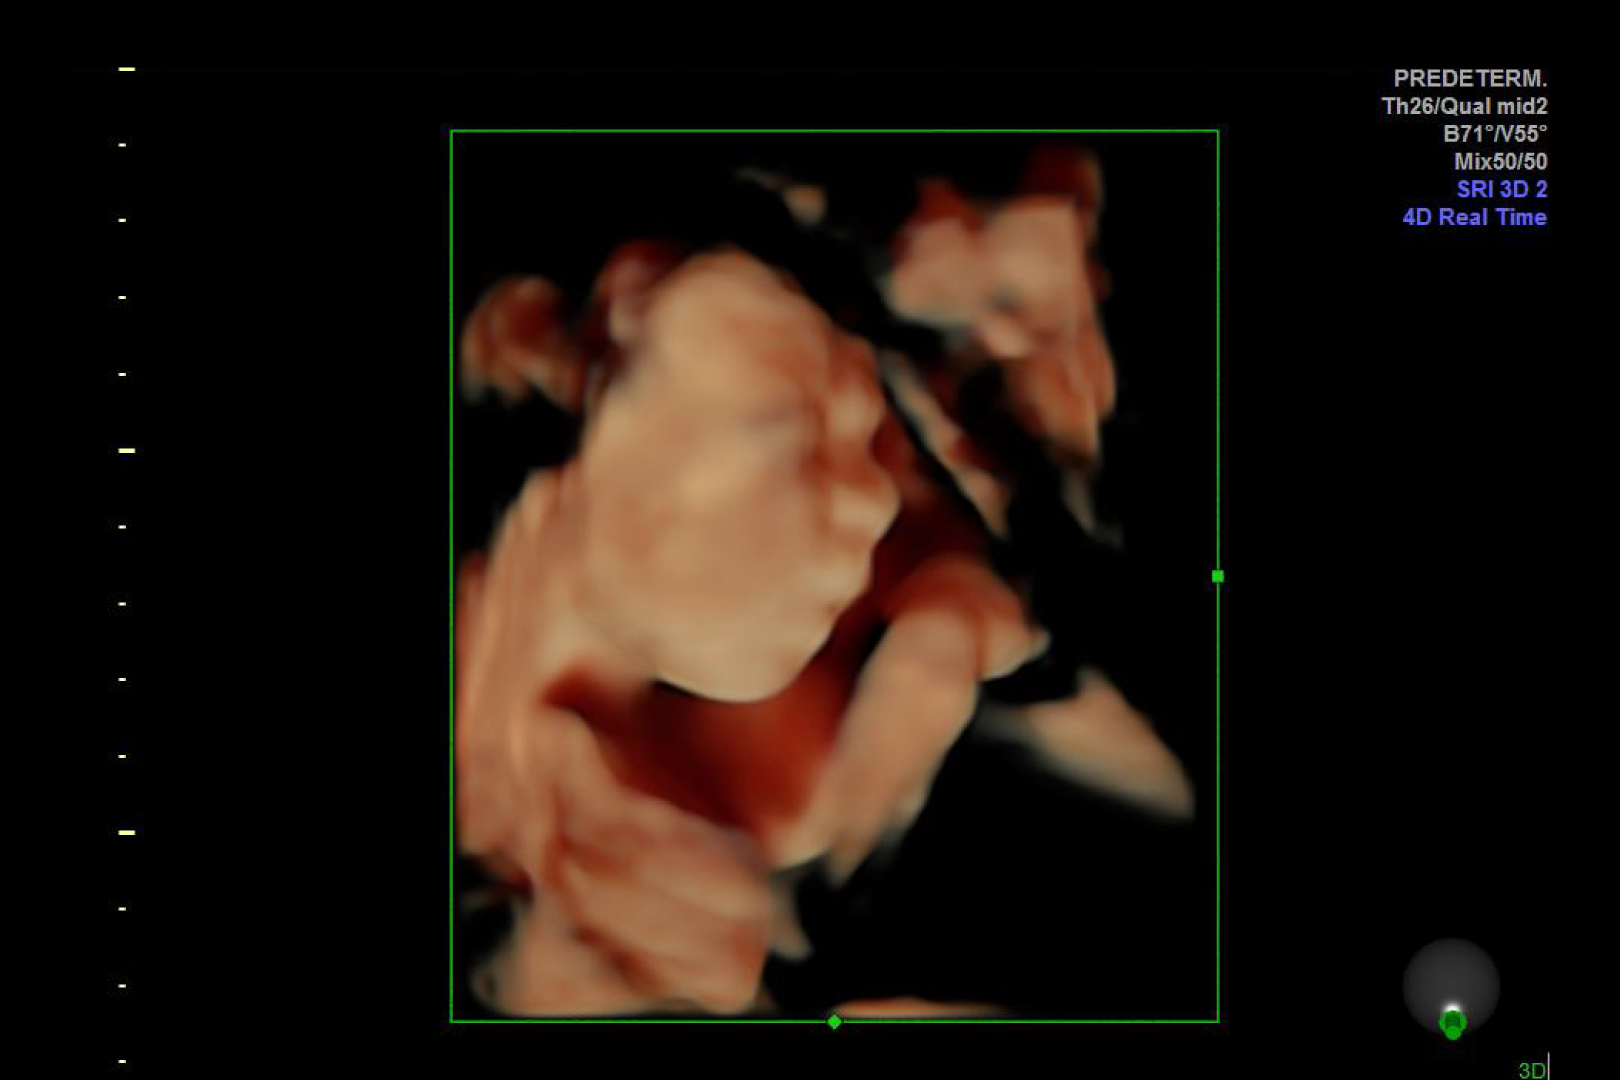

HD Live quinta dimensión, Imágenes de volumen con profundidad y claridad, que aportan un realismo anatómico para un mejor diagnóstico.